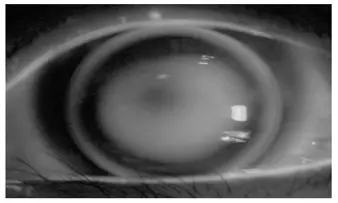

- (C) 螢光圖顯示垂直方向(上下)呈明亮亮帶、水平方向(左右)中央呈暗帶承壓——正是順規散光球面 RGP 的典型「啞鈴形(dumbbell pattern)」螢光圖。此圖型正確對應本題條件。✅